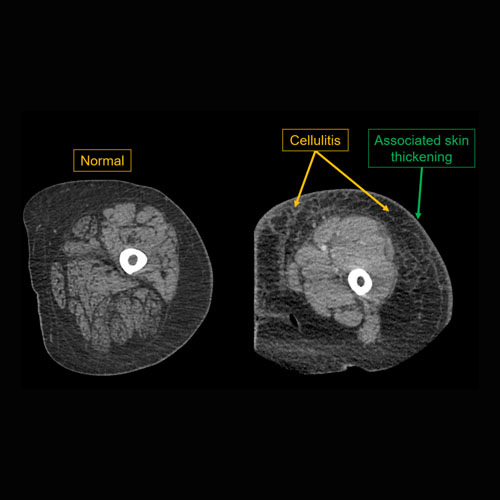

| Skin/Hypodermis | Correct Answer | Your Answer |

|---|---|---|

|

There is edema or hyperenhancement. |

Yes | NA |